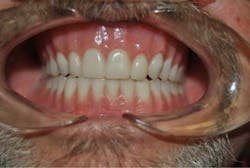

Kevin recently received his brand new set of teeth, and he can't stop smiling.

"I feel wonderful!" says Kevin, laughing. "I look in the mirror and I smile at myself. I can't believe that's me! And being able to smile at people, and they smile back. I don't scare them anymore."

His wife has also observed the changes that have occurred for her "miracle man," as she likes to call him.

"Oh, he's so proud of his teeth! He's so proud of them," says Cindy. "He looks in the mirror and he went for so long with bad teeth, then no teeth, and he got in the habit of covering his mouth with his hands when he would laugh. He loves his teeth! The people at Rodeo Dental are just amazing, amazing people."